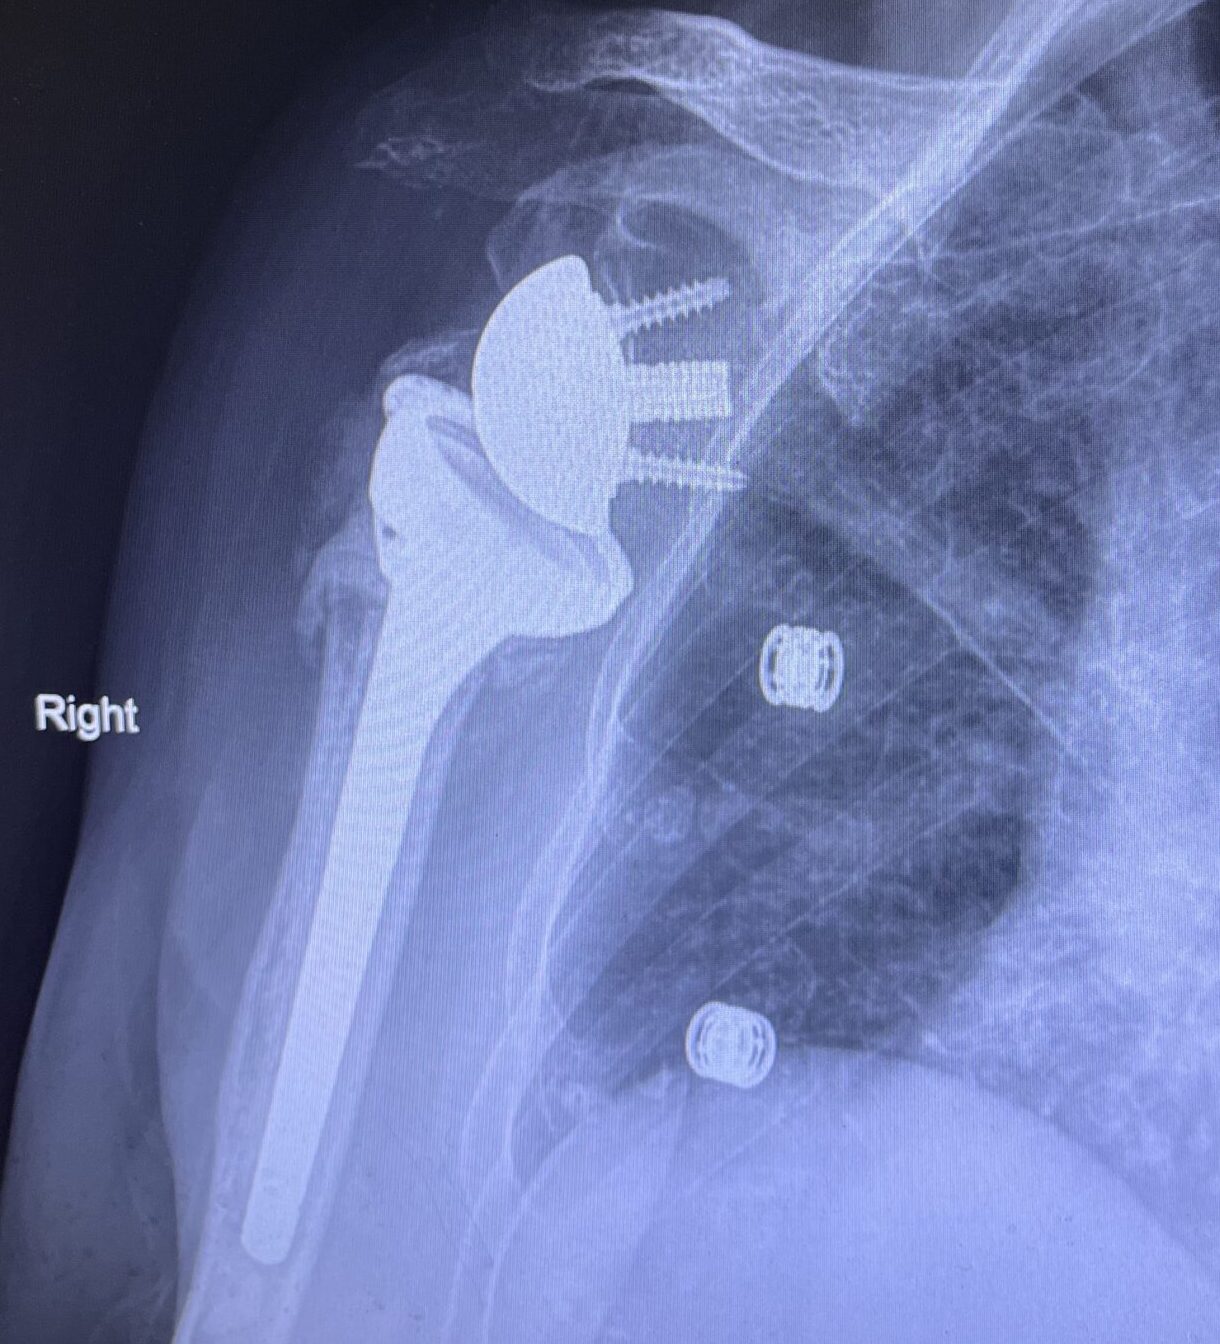

Αρθροπλαστική ώμου

Η άρθρωση του ώμου αποτελείται από τη σύνδεση της κεφαλής του βραχιονίου με την ωμογλήνη της ωμοπλάτης. Όταν η άρθρωση υποστεί σοβαρή βλάβη και οι συντηρητικές θεραπείες ή η αρθροσκόπηση δεν έχουν αποτέλεσμα, η αρθροπλαστική ώμου προτείνεται για την ανακούφιση από τον πόνο και την αποκατάσταση της λειτουργικότητας του χεριού.

Η επέμβαση εφαρμόζεται κυρίως για σοβαρές περιπτώσεις, όπως η οστεοαρθρίτιδα, η ρήξη του στροφικού πετάλου, η άσηπτη νέκρωση κεφαλής βραχιονίου και μαζικές ρήξεις τένοντα. Το 80% των περιπτώσεων αφορά ανάστροφη αρθροπλαστική, ενώ το υπόλοιπο 20% ανατομική αρθροπλαστική.

Η ανατομική αρθροπλαστική προτείνεται όταν η οστική δομή είναι καλή και το τενόντιο πέταλο ανέπαφο. Αντικαθίστανται η κεφαλή του βραχιονίου και η υποδοχή, συνήθως με μεταλλικά και πλαστικά εμφυτεύματα. Αντίθετα, η ανάστροφη αρθροπλαστική είναι ιδανική για εκτεταμένες βλάβες τένοντα ή σοβαρή φθορά της άρθρωσης, αντιστρέφοντας τις αναλογίες της άρθρωσης.